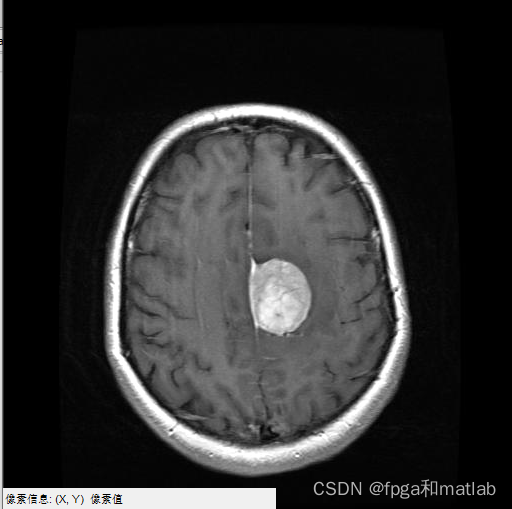

三、测试结果

通过matlab2021a仿真结果如下: